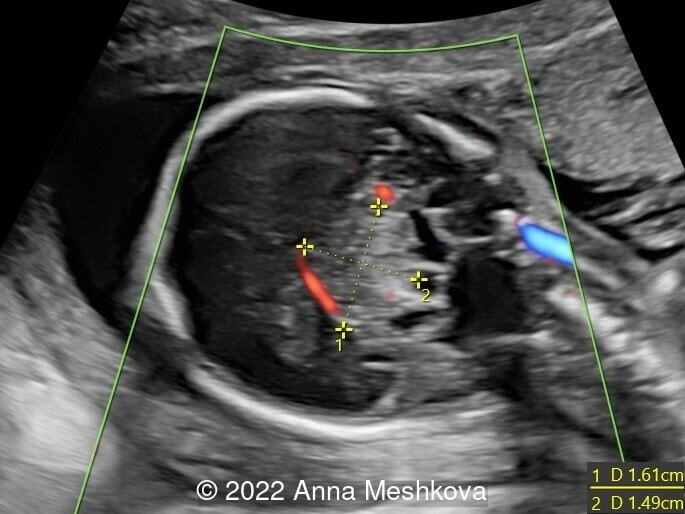

Case Report: A 23-year-old G1P0 with no remarkable medical history was scanned at our unit at 18 weeks of gestation. Ultrasound examination at the first screening and at 17 weeks were reported to be normal.

We present a case of intracranial teratoma.

Ultrasound imaging revealed the lesion approximately 26mm x 17mm x 23 mm located in the middle of the brain. The solid hyperechoic component measured 15mm x 16 mm. It was well defined, rounded, echogenic and heterogeneous with spots of hyperechogenicity. Color Doppler examination showed the presence of vascularization in the lesion. The other cerebral structures had a normal appearance, but some of them were compressed and displaced by the lesion. There was no extracranial abnormality.

The lesion was suspected to be a cerebral tumor due to its solid features and the presence of vascularization. Differential diagnoses were cerebral hemorrhage. Because of the early appearance of the lesion and its significant size, the prognosis was considered to be poor. A termination of pregnancy was discussed with the parents and was carried out at 19 weeks of gestation. Postmortem examination confirmed the diagnosis of intracranial teratoma, containing lung, bone, cartilage and neuroectoderm, with destruction of the central and right cerebral structures. Also the structures of the posterior fossa were displayed toward the cisterna magna.